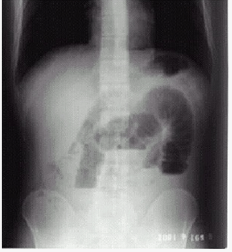

- 单项选择题病史:男性,46岁,腹胀、腹痛3天,停止排便。诊断:()

D、肠梗阻

- D